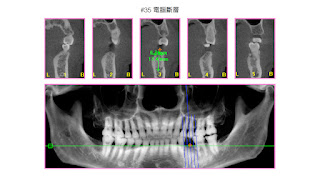

小臼齒立即植牙案例分享

• 小臼齒立即植牙案例分享